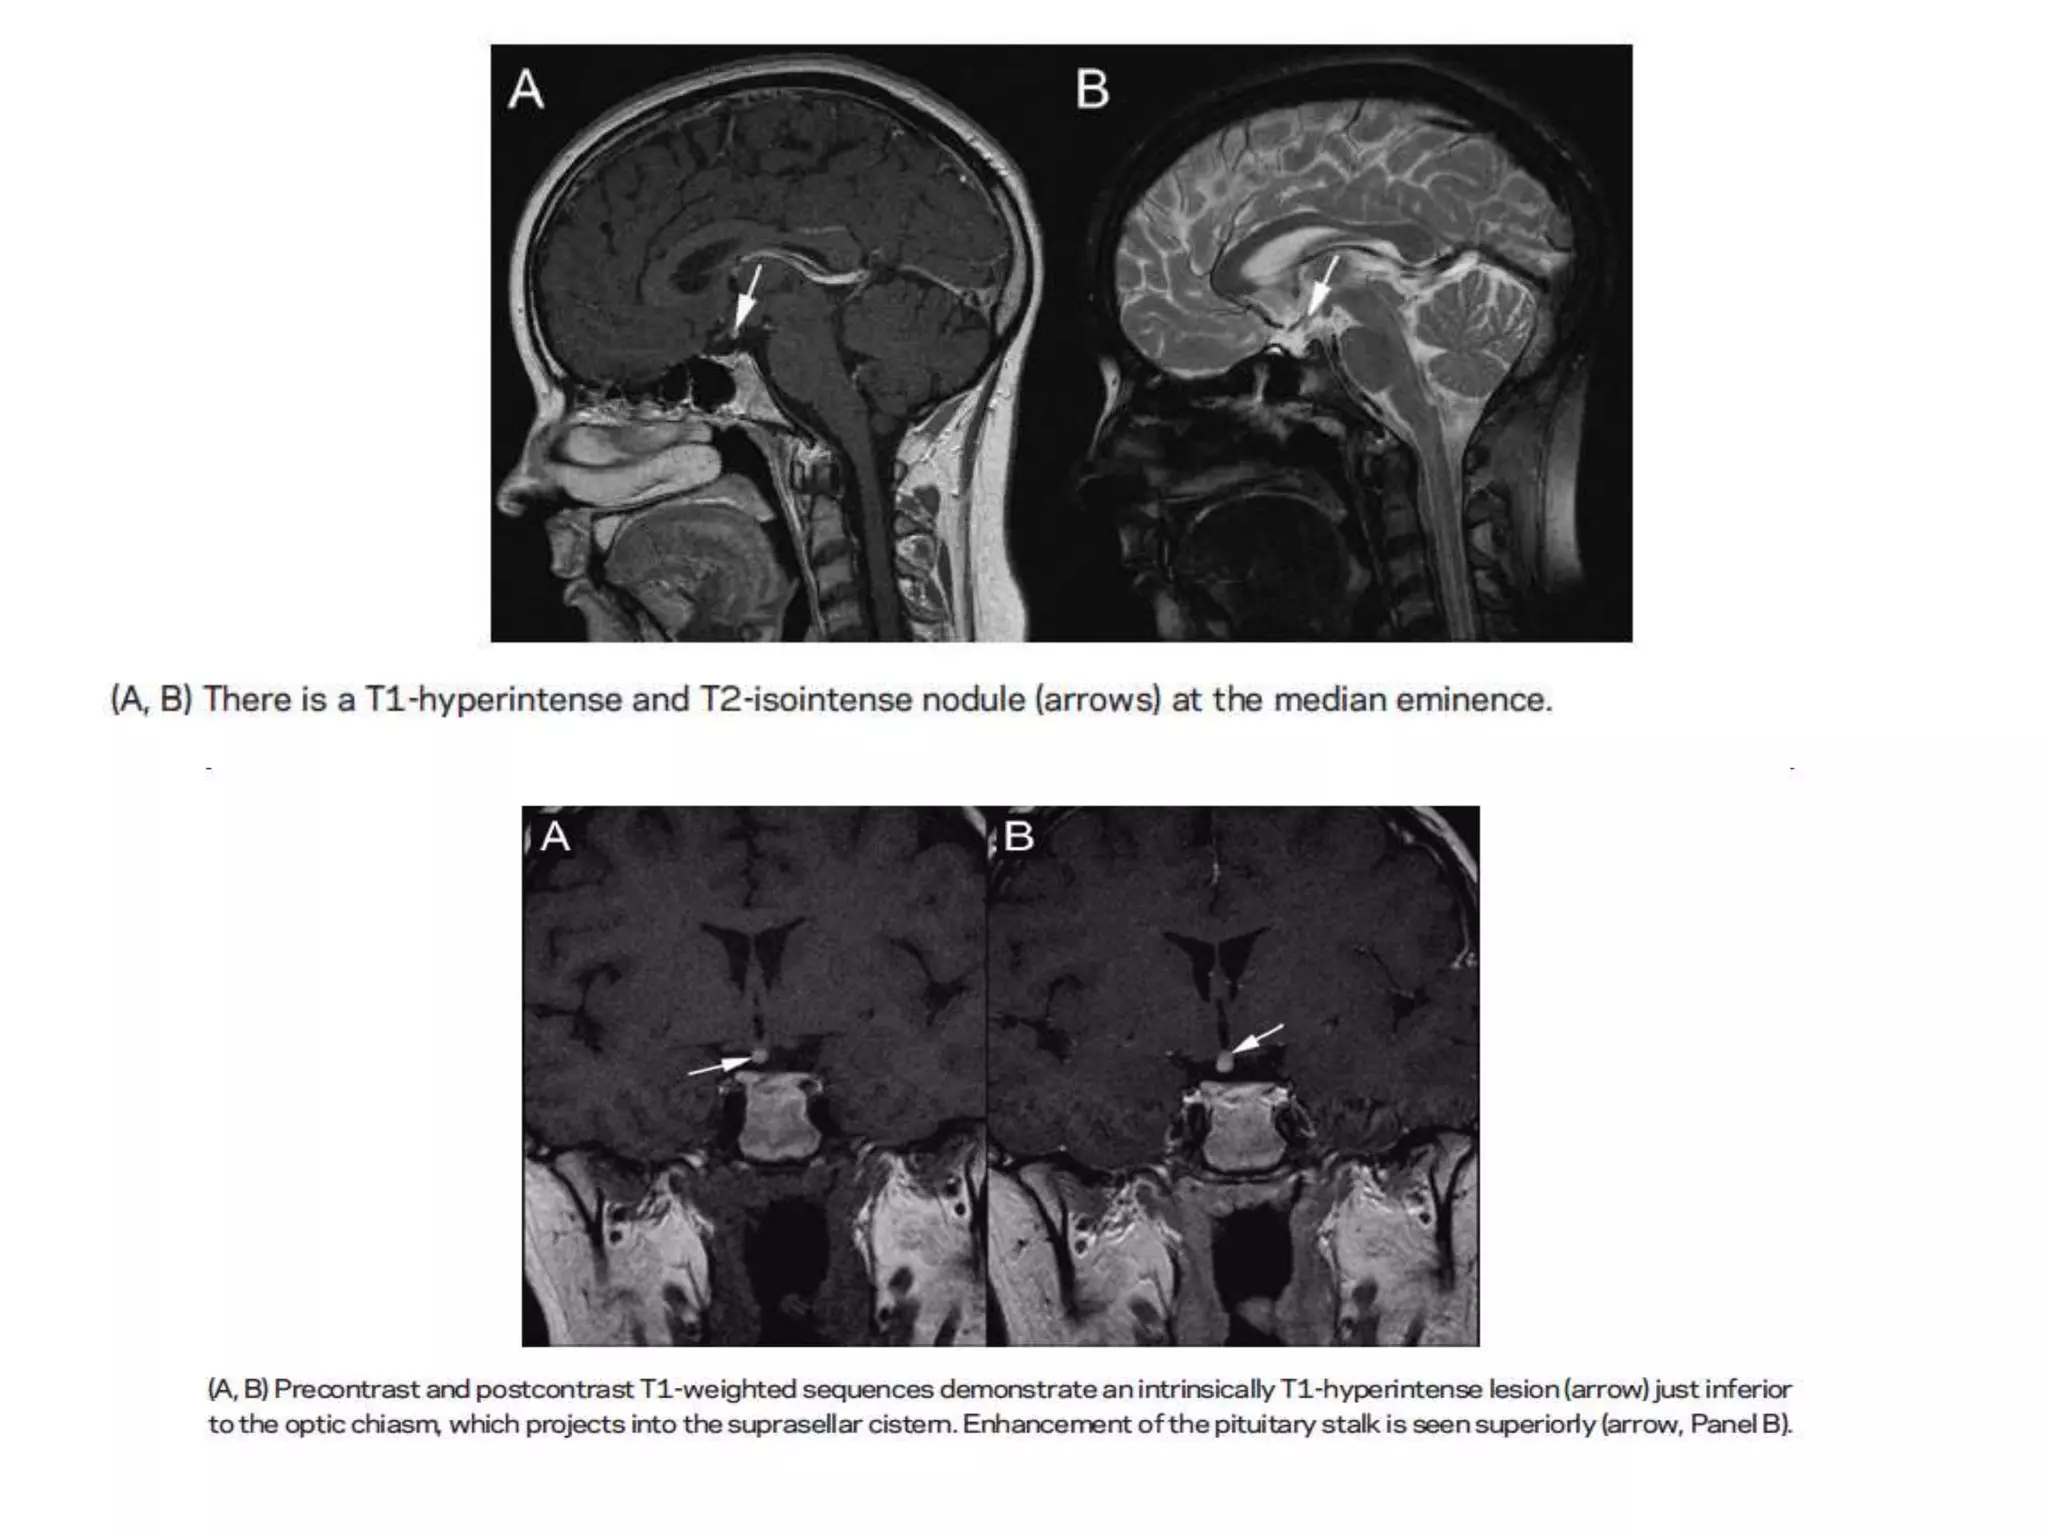

1) Ectopic posterior pituitary

Absent normal posterior pituitary

Bright spot within the sella with ectopic bright

signal at another site (such as the median

eminence) on a weighted magnetic resonance

Development:

Incomplete caudal extension of the diencephalon

during embryogenesis

Effect:

Pituitary dwarfism

Lack of growth hormone

1) Ectopic posteriorpituitary Absent normal posterior pituitary Bright spot within the sella with ectopic bright signal at another site (such as the median eminence) on a weighted magnetic resonance Development: Incomplete caudal extension of the diencephalon during embryogenesis